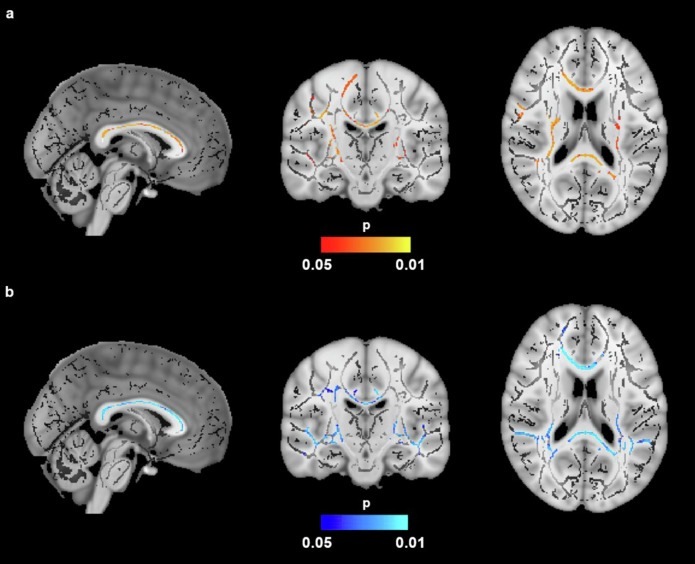

肥胖是痴呆的一个风险因素,它会造成慢性炎症状态,导致白质损伤。边缘密度成像(EDI)是一种新的技术,已经证明了量化WM变化的可靠性。30名肥胖和20名认知正常的非肥胖成年人接受了结构和扩散加权磁共振成像。内脏脂肪组织(VAT)和皮下脂肪组织(SAT)通过体素分析套件进行定量,分离脂肪组织和非脂肪组织的信号强度。扫描由管道(MaPPeRTrac)处理以生成EDI。在肥胖的参与者中,VAT/SAT比率和EDI之间存在负相关,而在非肥胖的参与者中没有看到。此外,男性的EDI比女性低。这项研究的结果表明,肥胖,通过WM损伤,可能增加痴呆的风险,性别是一个潜在的差异因素。EDI在描述肥胖和痴呆的神经病理学方面显示出了希望。

Obesity is a risk factor for dementia, creating a chronic inflammatory state that results in white matter (WM) injury. Edge density imaging (EDI) is a novel technique that has demonstrated reliability in quantifying WM changes. Thirty obese and 20 non-obese cognitively normal adults underwent structural and diffusion-weighted magnetic resonance imaging. Visceral adipose tissue (VAT) and subcutaneous adipose tissue (SAT) were quantified via VOXel Analysis Suite by separating signal intensities of adipose and non-adipose tissue. Scans were processed by a pipeline (MaPPeRTrac) to generate EDI. Among obese participants, there was a negative association between the VAT/SAT ratio and EDI, which was not seen among non-obese participants. Additionally, males had decreased EDI compared to females. The results of this study suggest that obesity, through WM damage, may confer increased risk of dementia, with sex as a potential differential factor. EDI demonstrates promise in delineating the neuropathology of obesity and dementia.